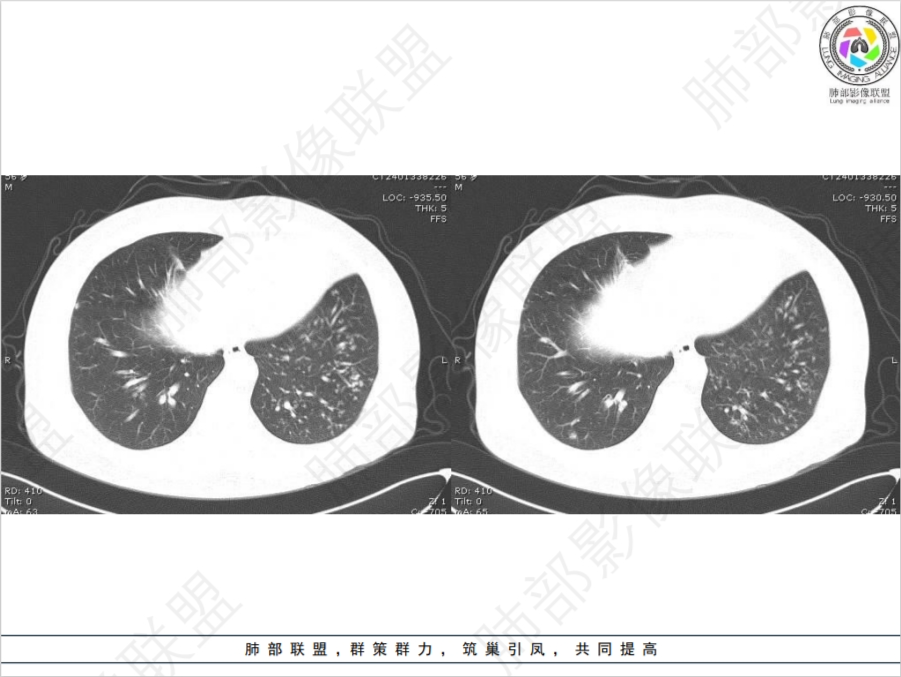

病灶多灶性,多态性,这个病例如何确诊肺结核?

治疗两星期的肺结核ct对比